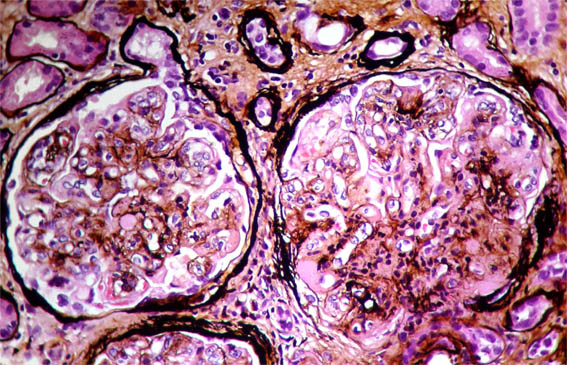

Figure 6. Methenamine-silver stain, X400.